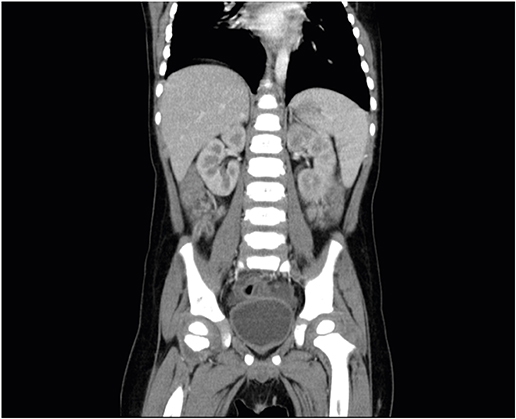

However, on hospital day (HD) #2, the patient exhibited more severe abdominal pain than that on the initial assessment. Physical examination revealed focal tenderness in the both lower quadrants with localized guarding and no evident rebound tenderness. Contrast abdominal computed tomography (CT) demonstrated a dilated, fluid filled tubular structure in the lower right quadrant indicative of appendicitis (Fig. 3). On the basis of these findings, the patient was transferred to the department of general surgery and undertaken laparoscopic appendectomy. The laparoscopic findings included wall thickening in the cecum and mild inflammation in the appendix. Pathologic examination of the resected segment revealed telangiectasia of the serosa, and the lumen contained suppurative exudate with acute inflammation, but no thrombotic microangiopathy was observed (Fig. 4).

Fig. 3

Enhancing wall thickening and fluid filled dilatation of appendix on abdominal-pelvis computed tomography.